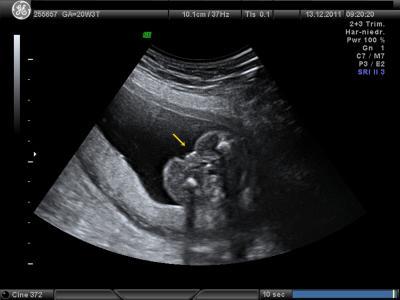

hallo, es war toll ! alle werte sind in ordnung, keine auffälligkeiten, alles zeitgerecht. hier ein paar werte: KU: 188,4mm FL : 32,9mm AU : 144,6mm gewicht ca. 370g und ist wird ein mädchen !!! hier das outingbild

Bild zu zurück von der FD ! - Forum für April - Mamis